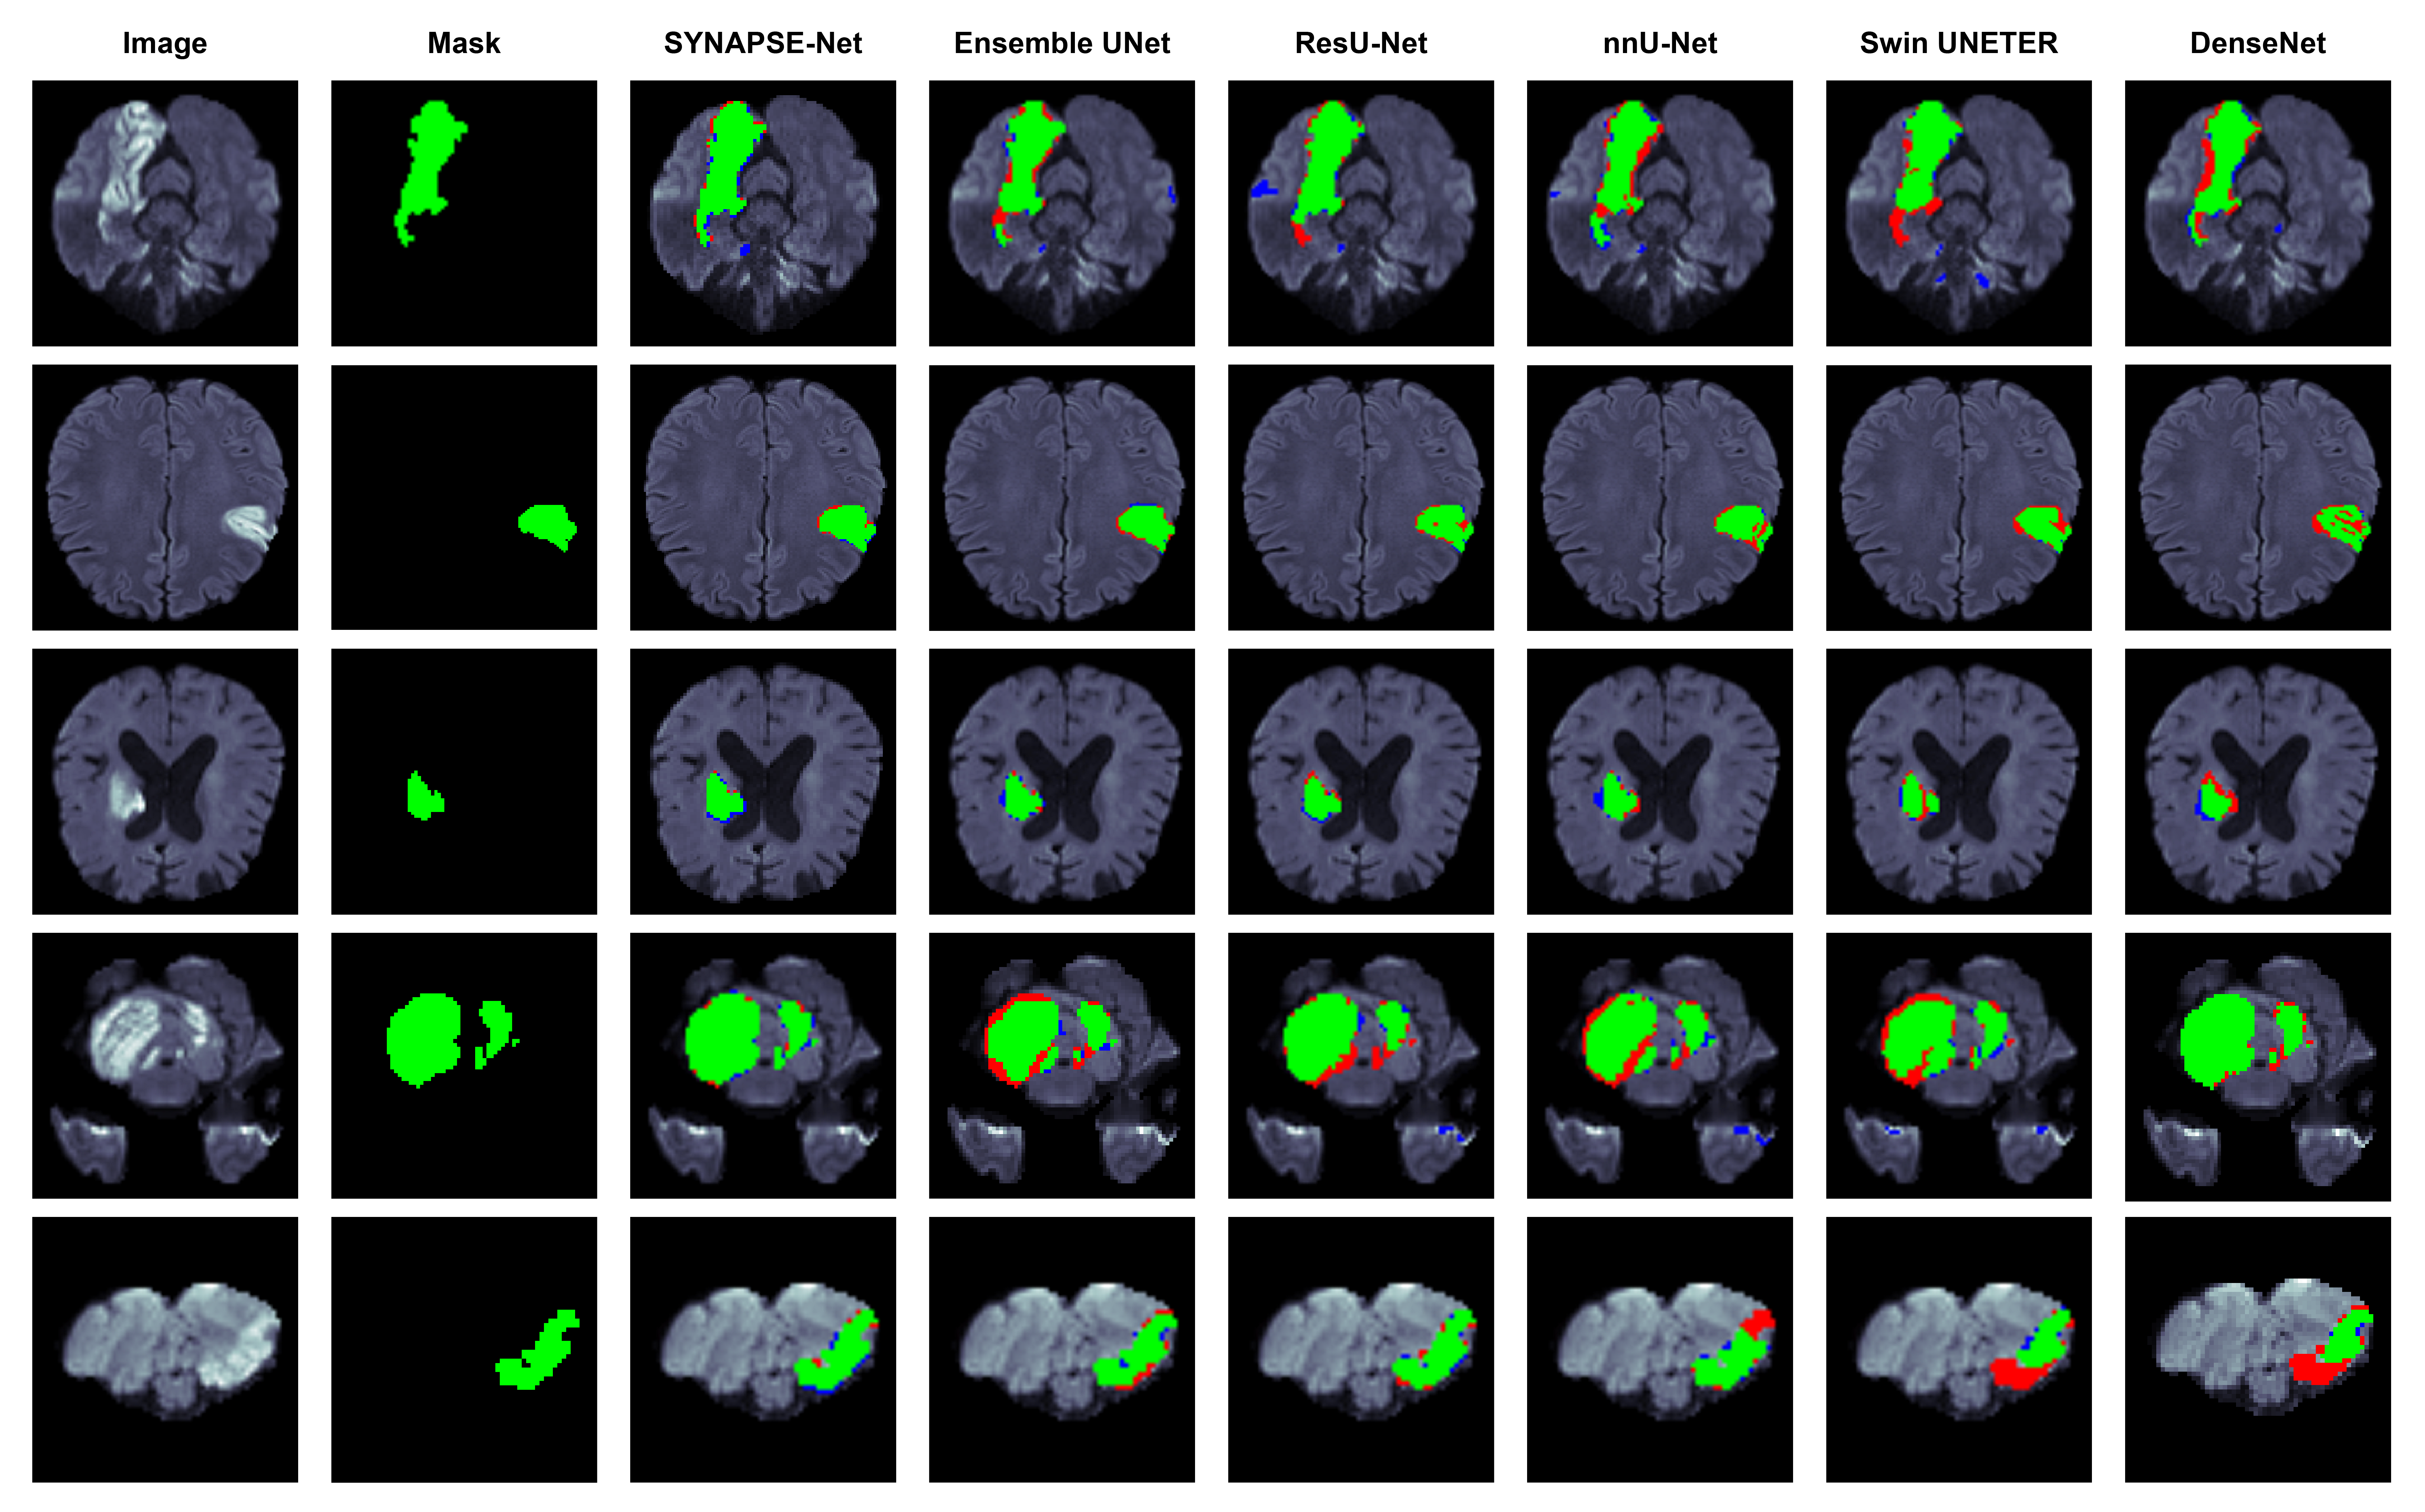

Refer to caption

Figure 5: Qualitative results of the architectural ablation study on the WMH dataset. Segmentation overlays show true positives (green), false negatives (red), and false positives (blue).

The baseline (1), which is the standard UNet++, had an acceptable Dice Similarity Coefficient (DSC) but poor precision, indicated by high HD95 and instability. Next, we evaluated the influence of our (2) advanced bottleneck that incorporates the multi-stream encoders, Swin Transformers, and the CMAF module. This addition yielded a significant performance boost, improving both mean DSC and HD95. The Swin Transformer’s capture of global context and CMAF’s effective fusion drive this performance boost. Finally, we evaluated the full SYNAPSE-Net (3), which integrates our novel hierarchical gated decoder. The results showed further improvement for the complete model, increasing the mean HD95 by 40% compared to the previous results. This is because the proposed hierarchical gating mechanism is an essential component for maintaining the precision of the results. By implementing high-level semantic features as a means of modulating the passage of low-level spatial information, the decoder defines intricate lesion borders more accurately. This can be observed in Figure 5 since the complete model can accurately delineate the boundaries of the lesions compared to the other models. Additionally, as evident from the boxplots in Fig. 6, the standard deviation of all metrics reached their lowest points, demonstrating that the complete architecture is the most robust and reliable.

The next study evaluated the effects of our novel architectural components, using the complete training pipeline on each setup. Quantitative results can be found in Table 4, and qualitative examples can be observed in Figure 5.